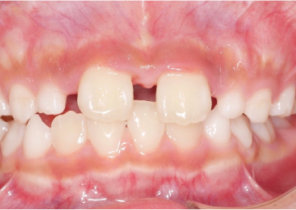

Informe de caso 1

10 años, 0 meses de edad, 18 etapas con dispositivos Invisalign Palatal Expander

Cortesía de la Dra. Sandra Khong Tai

Antes de la disyunción con el sistema Invisalign Palatal Expander

Después de la disyunción con el sistema Invisalign Palatal Expander

Después del tratamiento Invisalign First